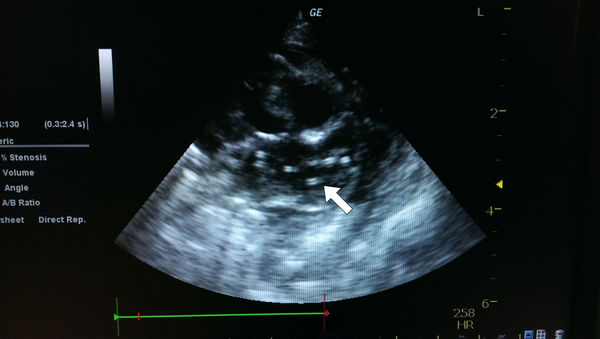

心臟胸腔科